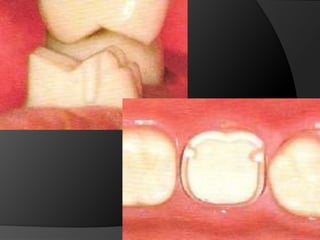

Reducción OclusalDebe tallarse suficiente tejido dental de la 	superficie oclusal de la preparación de tal 	manera que cuando la restauración se 	construya según la oclusión ideal,  tenga 	el grosor suficiente que prevenga su 	desgaste o su distorsión.

Reducción OclusalCorona en oro:     1,5 mm cúspide funcional				       1,0 mm cúspide no funcionalCorona en metales duros: 			       1,3 mm cúspìde funcionalCorona cerámica: 2,0 mm cúspide funcional				        1,5 mm cúspide no funcional

Si la superficie oclusal se hace plana, el metal en el área del surco de desarrollo será demasiado fino, con riesgo de perforación

Reducción AxialCuando la reducción axial es suficiente, las 	paredes de la restauración pueden tener 	un grosor satisfactorio sin sobrecontornos